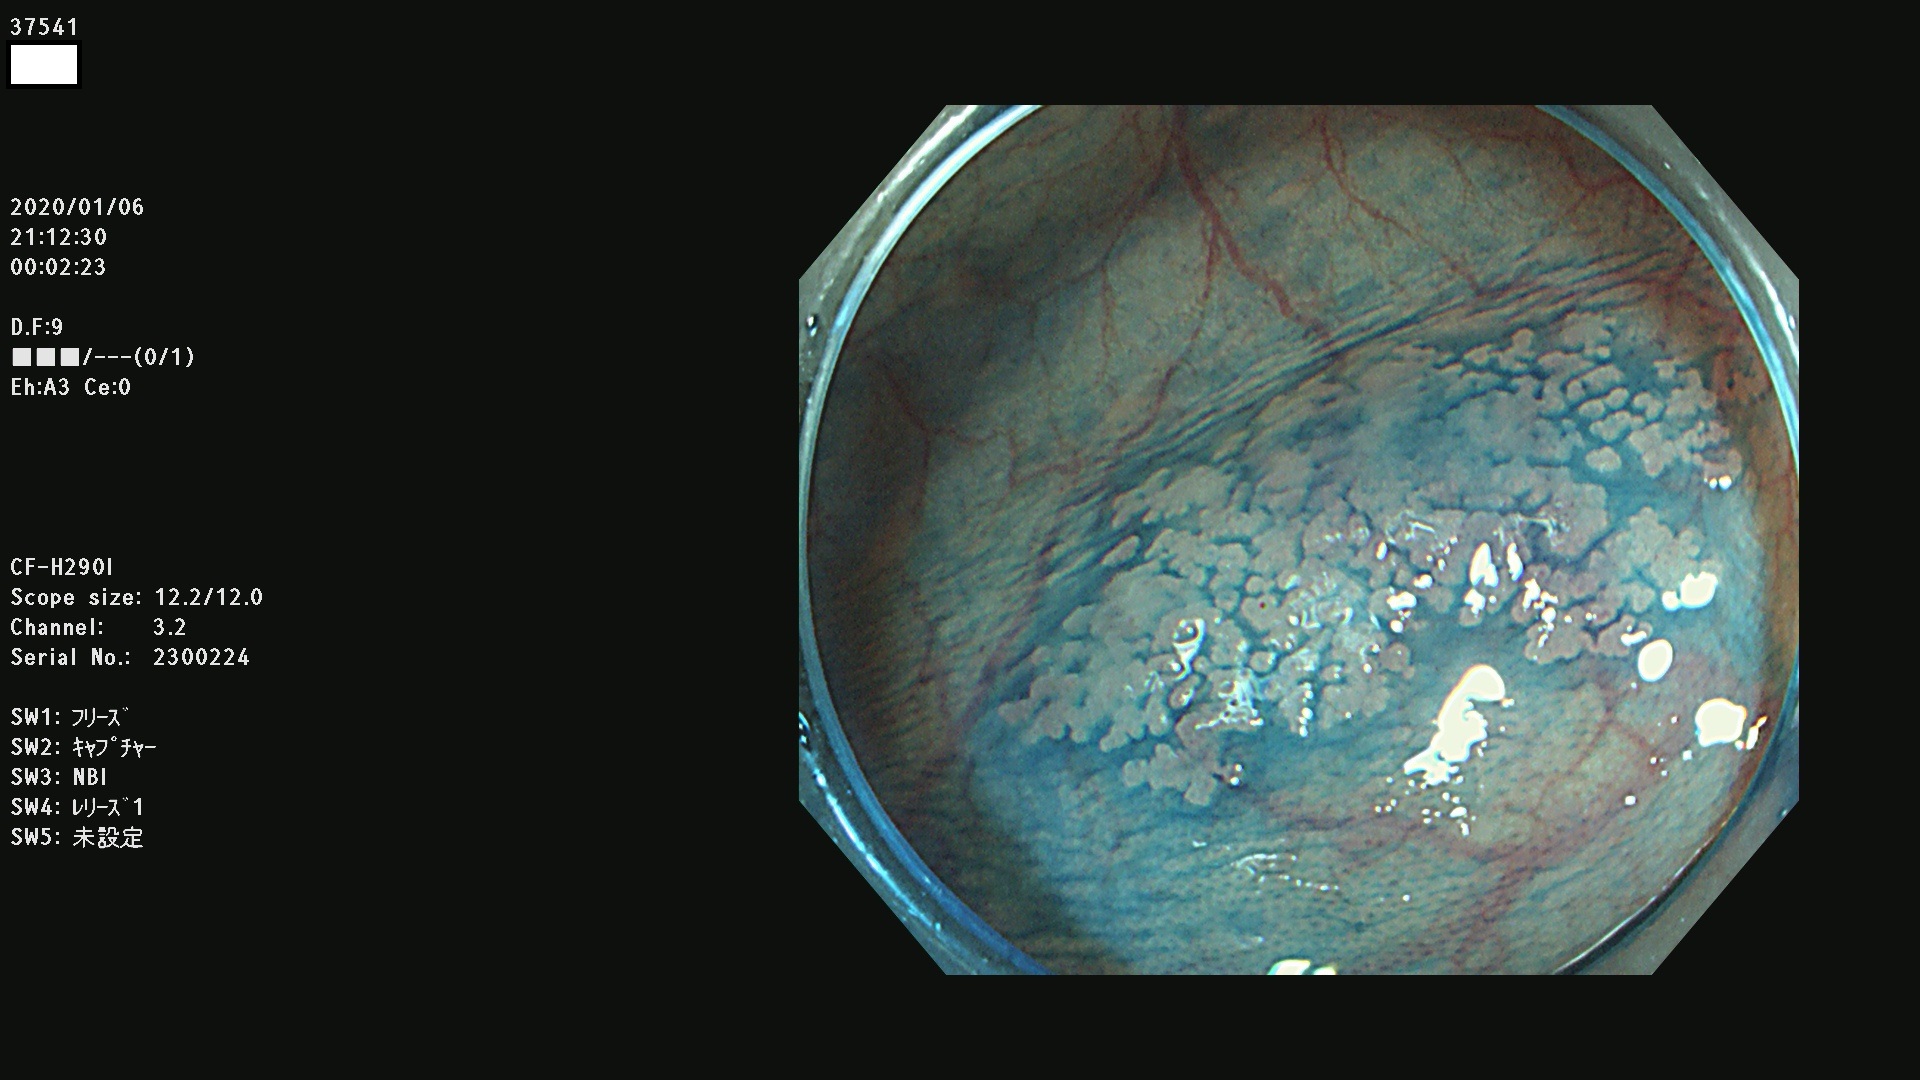

現在、最も広く使われているH290スコープ(細径)の画像

EZ1500DI(太径)の画像。この方は「癌に近い高度異形腺腫」なのですが、大学へ紹介するも再発見できませんでした。